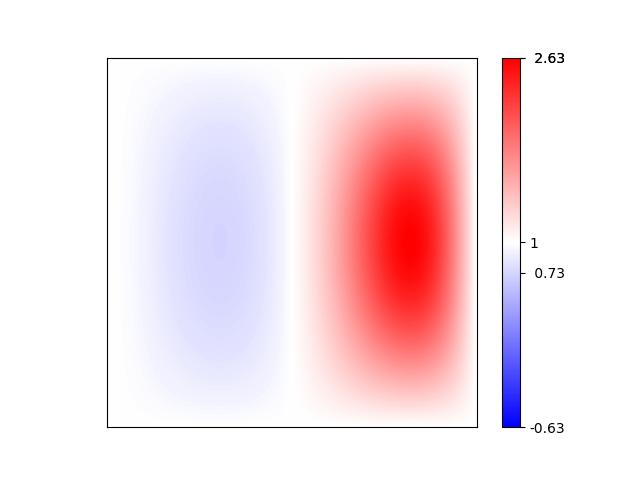

Intensity distortions, that shift, stretch or compress the histogram, such as gamma transforms or an intensity shift, can appear between different scanning parameters, because MR does not guarantee a fixed intensity scale. For gamma transforms, images are first normalized by MinMax to range (0, 1). This ensures, that the intensity value range is unchanged under gamma transformation. Then, the intensities are scaled back to the original intensity range. Intensity shifts are modeled by adding a fixed value to the intensity value of all pixels.

Further distortions, that represent typical acquisition artifacts of MR images are ghosting, stripe and bias field artifacts. Ghosting artifacts appear as shifted copies of the image, arising from erroneous sampling in the frequency space. Single pixel artifacts in the frequency space cause artificial stripes. Bias fields appear as low frequency background signals, that we model by multiplying with an exponential of a polynomial function of degree three (see Fig. 1). All of these distortions may moderately expand the intensity range of the distorted image compared to the reference image.

5 Adverse Examples

In the following, special characteristics of the analyzed metrics, which can be derived from their definition or the experimental results above, are show-cased. We present adverse examples (see Fig. 2-6), where similarity metrics do not perform as intended or expected.